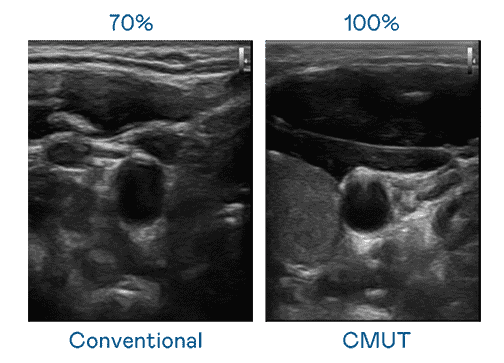

CMUT 技术是一种用电容式微机电元件来产生超音波讯号的技术。。。。与传统 PZT 压电式技术相比,,,,CMUT 频宽增加 30%,,更宽频的超音波讯号让影像解析度大幅提升,,,,是实现高影像品质医疗超音波扫描、、促进精准医疗发展的关键技术。。。。

超音波影像的解析度高低,,,首先取决于探头能发出的讯号频宽。。。欧陆注册 CMUT 可提供高清晰的超音波讯号,,,提供高频宽、、、、高灵敏度、、、影像纹理细节更高的超音波影像,,,,协助医护人员缩短影像判读时间及利用精准的医疗影像进行诊断。。。。